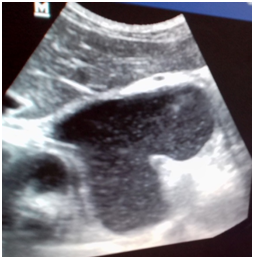

Thoracoabdominal scan is performed to a fine. Elle semiotics revealed a hypo dense formation (10 UH) volume of 400cc, the tail of the pancreas higher growth, reaching the mediastinum where it is in contact with the vena cava lower and the descending aorta. She pushes the stomach and esophagus. Its wall is measured 3.5mm and is calcified in places. The pancreas is calcified as a whole. The hypothesis of a false pancreatic cyst of thoracoabdominal seat on chronic pancreatitis was confirmed. The patient underwent drainage of pseudocyst laparoscopically and is out of the hospital at D7. He is fine.

Figure 3 & 4 Thoraco-abdominal scanner with injection at arterial time: Presence of a fluid collection beginning at the tail of the pancreas with extension in the thorax. Pancreas completely calcified.

The imagery in this study combined abdominal ultrasound, chest X-ray barium swallow the one hand and the scannerd'autre hand. Abdominal ultrasound revealed the presence of many pseudo-pancreatic cysts in abdominal location. It is limited in the search for false pancreatic cysts intra thoracic where CT and MRI are more efficient.13,15,16 The scanner achieved in this patient confirmed the presence of the false cyst with a finer semiotics and especially its relations with the various neighboring structures (inferior vena cava, descending aorta, left ventricle) unlike abdominal ultrasound, radiography thoracic (front / profile) and the barium swallow.